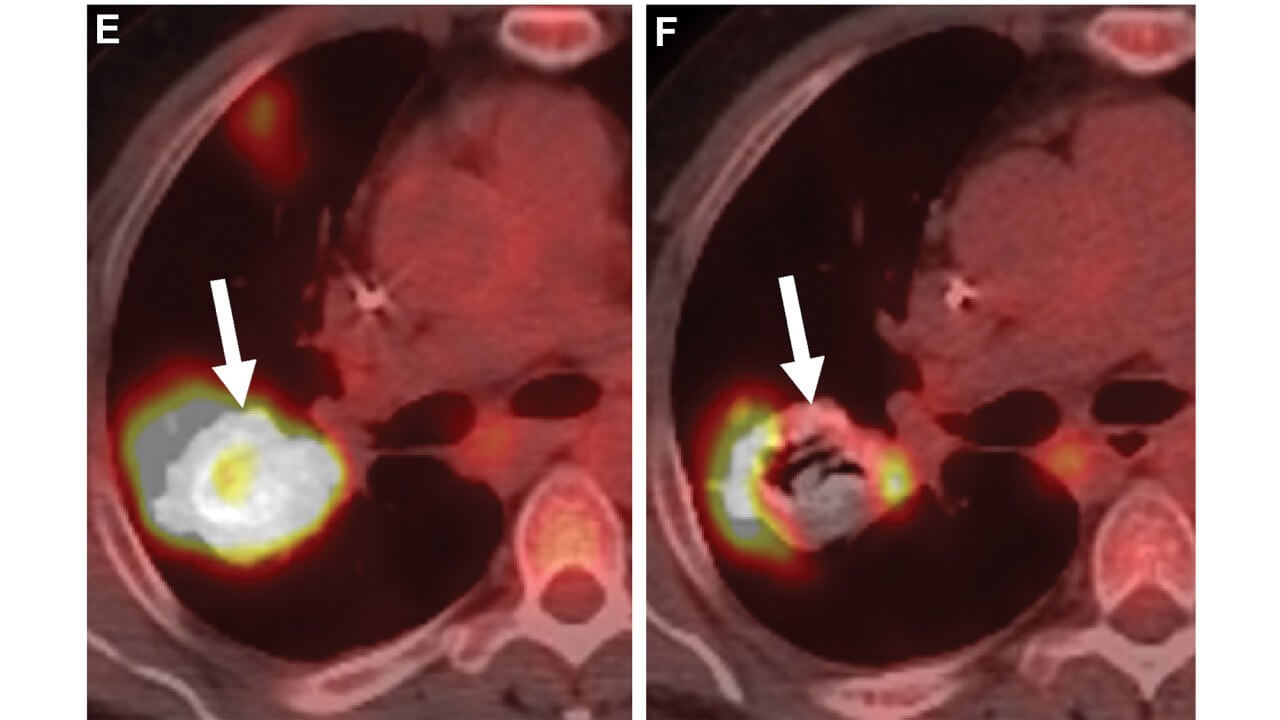

When lung metastases are suspected, a chest CT scan or PET scan is often ordered. If the scan reveals a tumor and the doctor has confirmed that it is cancerous, it is also important to confirm whether it is primary lung cancer – cancer that begins in the lungs – or breast cancer that has spread to the lungs. The treatment of primary lung cancer is different from treat metastatic breast cancer diagnosis that has spread to the lungs.

Diagnostic tools include Chest CT, PET-CT, MRI (in selected cases), biopsy (if necessary to clarify the diagnosis), molecular genetic, cancer markers and immunohistochemical tests.